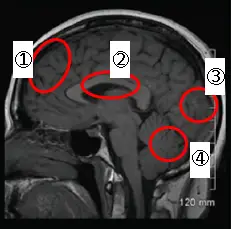

圖片為腦部磁振造影(MRI)矢狀切面(sagittal view),以紅色橢圓圈出四個腦區,編號如下:

- ①:位於最前方(anterior)的腦區,對應額葉(frontal lobe),包含前額葉皮質(prefrontal cortex, PFC)

- ②:位於中央偏上方,對應**頂葉(parietal lobe)**及中央區域

- ③:位於後方(posterior),對應枕葉(occipital lobe)

- ④:位於下後方,對應小腦(cerebellum)

本題關鍵在於辨識哪個標號對應到負責高階認知功能的額葉,圖中①明確指向大腦最前端的額葉區域。